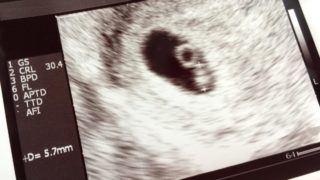

妊娠中絶が手術でなく、飲み薬で行うことができるという薬が国内初、2022年以降に承認されるかもしれない(2022年3月現在まだ未承認)

婦人科看護師、きくとまです。私はこれまで多くの患者さん、妊婦さんを見てきました。そんな中で思いもよらず妊娠してしまい、赤ちゃんを育てるお金もなく、また色々な事情で、仕方なく中絶を余儀なくされた方もいらっしゃいます。望まない妊娠をしてしまった...